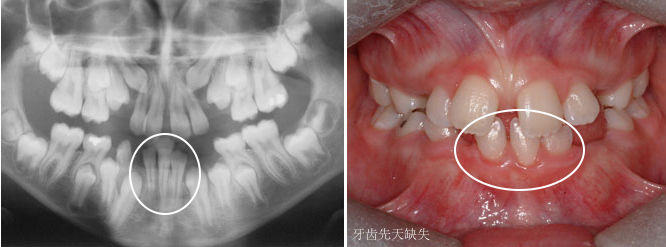

什么是牙齿迟萌?

如果牙齿比平均该长牙的年龄,晚了12个月还没有长牙的话,叫做牙齿迟萌。造成牙齿迟萌的原因有很多,比如,多生牙、牙瘤、囊肿会导致牙齿迟萌。

如果你家孩子比平均该长牙的年龄,晚了12个月还不长牙,你需要及时带孩子看牙医了。牙医一般会拍牙片来看看牙床内是否有未萌出的牙齿。